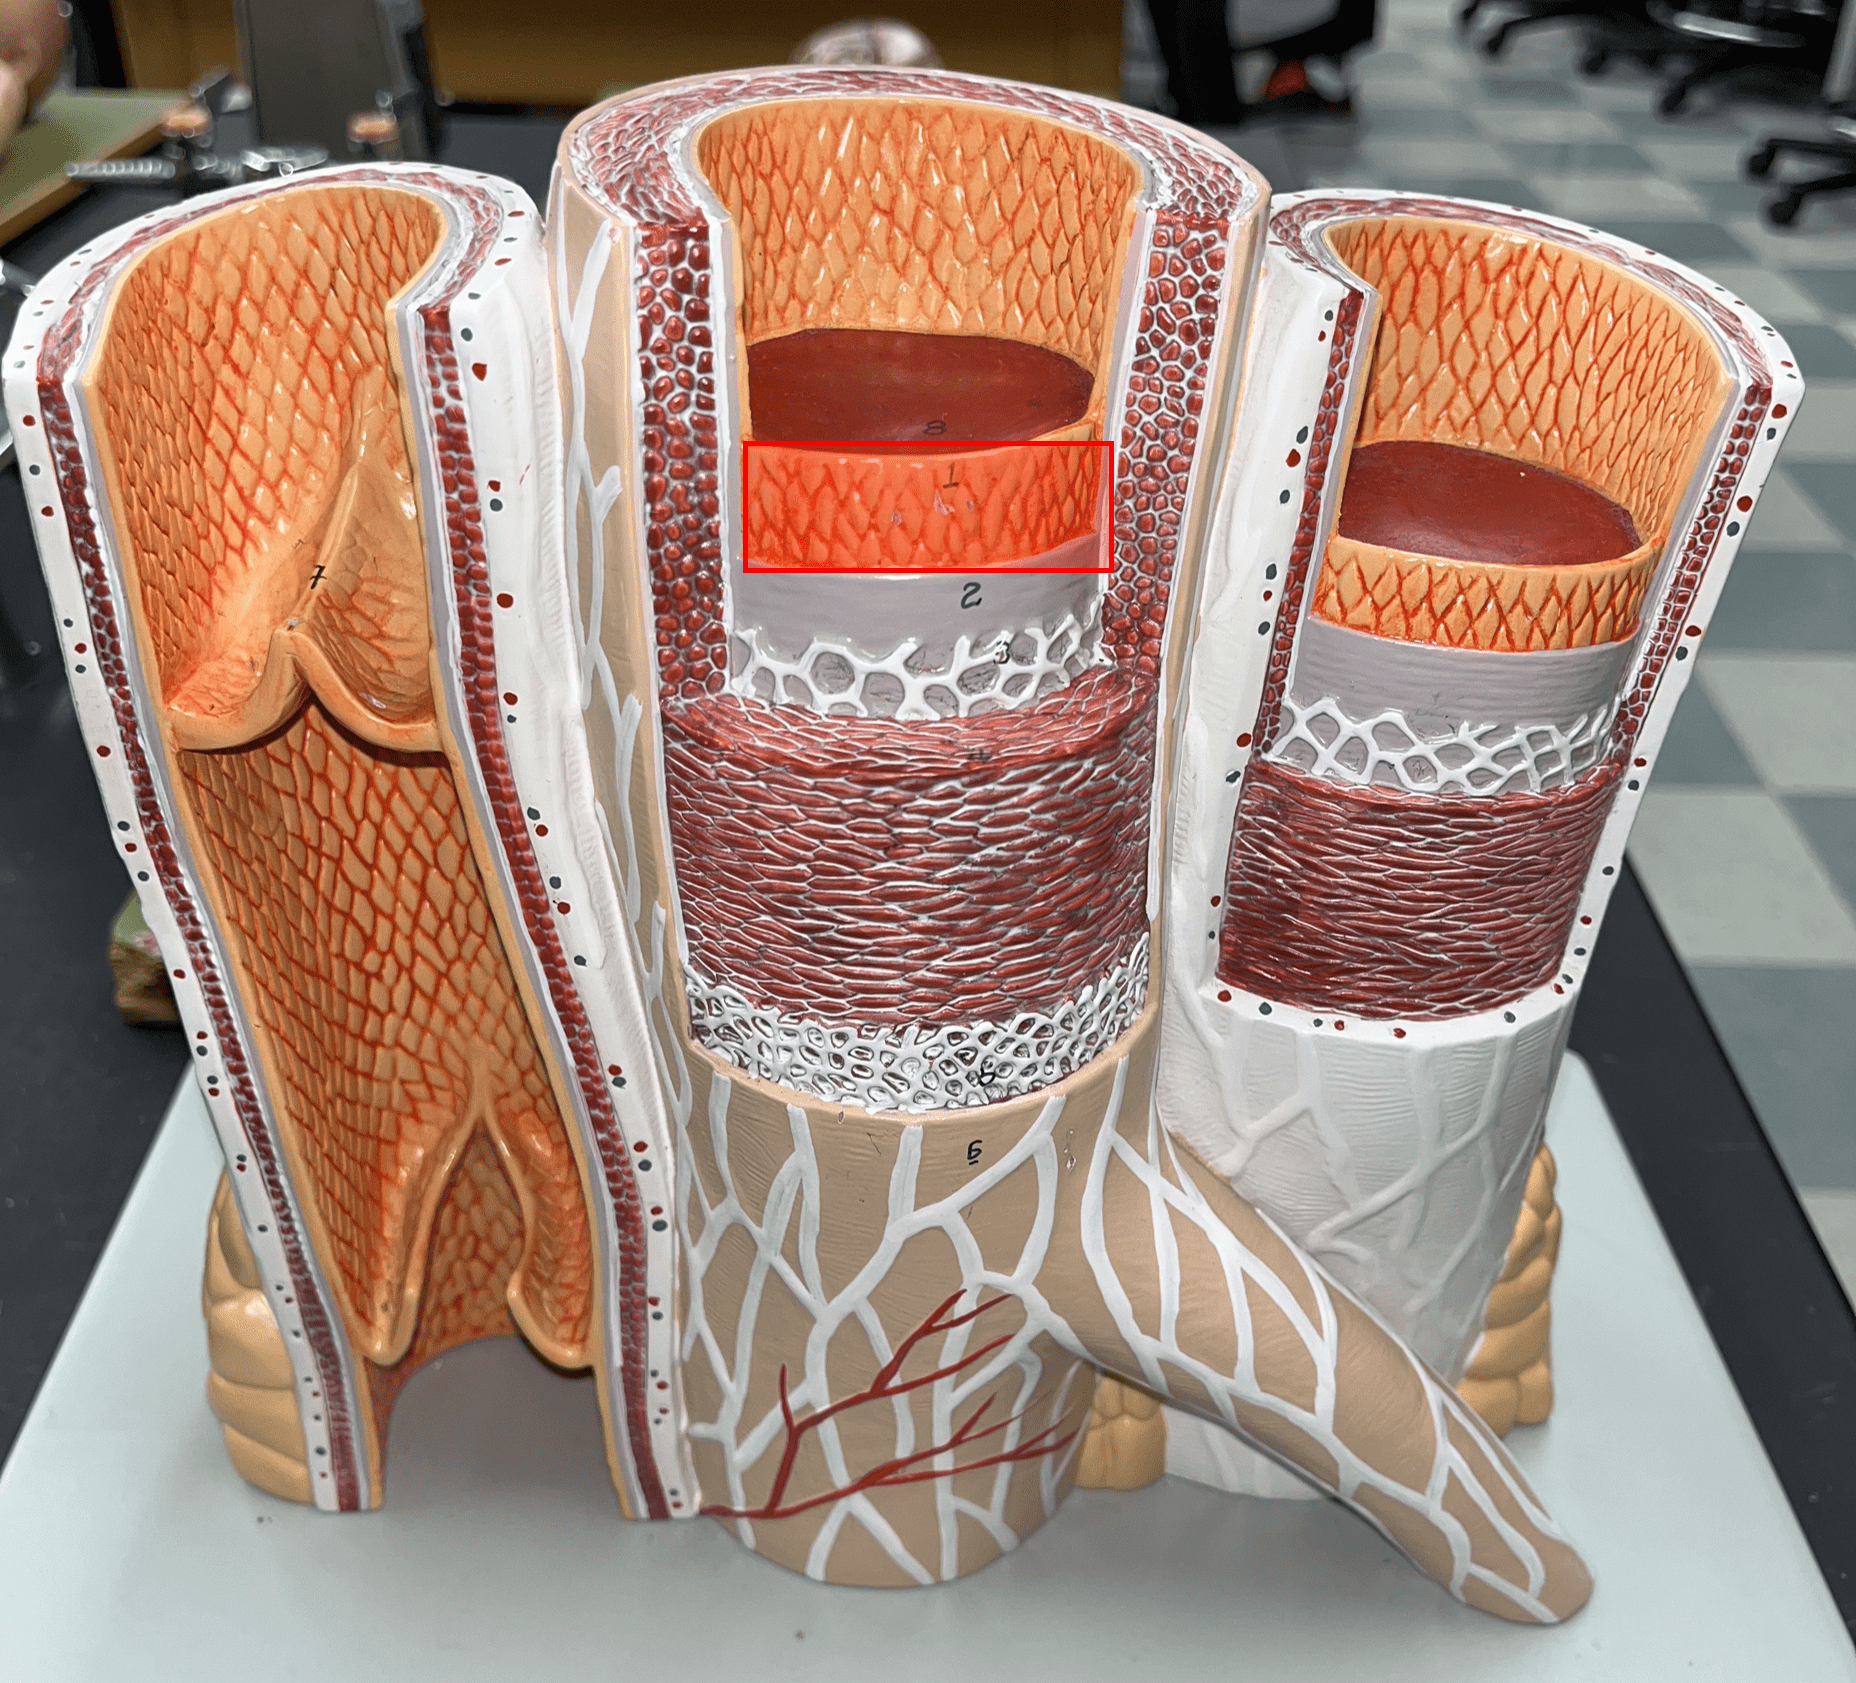

1

tunica externa

7

external elastic membrane

tunica media

internal elastic membrane

10

tunica interna

11

endothelium